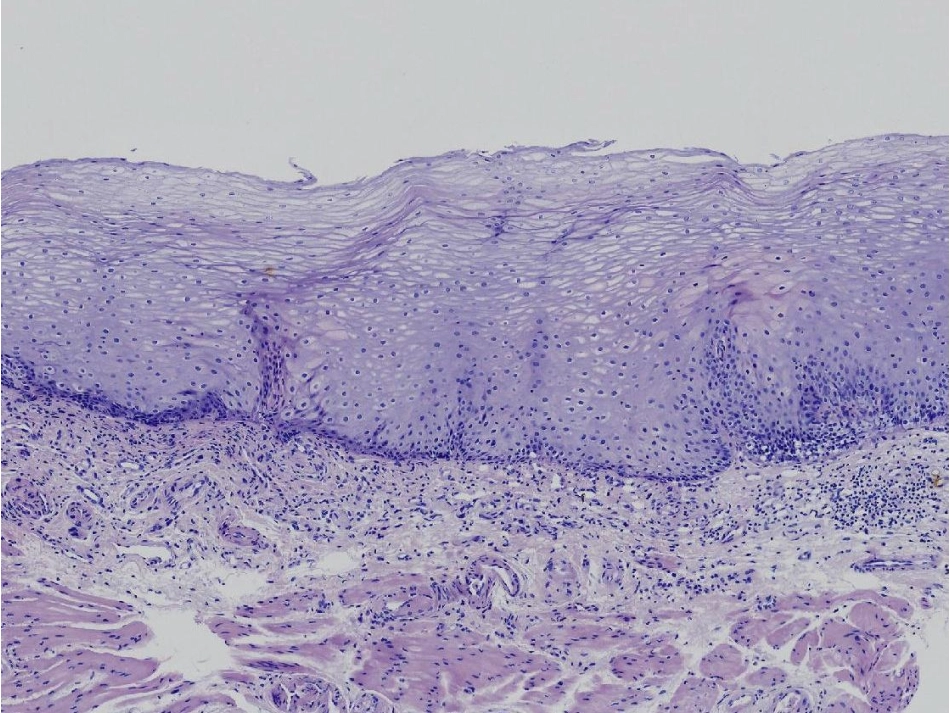

学习目标:1.准确识别食管的结构层次2.掌握放大NBI下的IPCL分型3.能解读食管早癌的病理结论食管腺食管腺的AB染色食管腺的导管导管周围聚集的淋巴细胞于固有层分布的食管贲门腺AB-PAS染色阳性提示腺体构成主要为中性黏液细胞(PAS染色阳性,呈紫色),少量为酸性黏液细胞(AB染色阳性,呈蓝色)鳞状上皮层基底层细胞(立方型、矮柱状)棘细胞层细胞(多边型)表层未角化扁平细胞(梭型)棘细胞层深部及基底层细胞为生发层,具有细胞分裂功能。表浅癌及其对应深度划分表浅癌定义为局限于粘膜或粘膜下层,无论有无淋巴结转移。既往的早癌是指表浅癌且无淋巴结转移。最近早癌定义为粘膜内癌而无论淋巴结有无转移。食管表浅癌的肉眼分型胃肠上皮肿瘤的Vienna分类修订版Vienna分类临床处理1.无肿瘤1.选择性随访2.不确定肿瘤2.随访3.黏膜低级别瘤变3.内镜切除或随访低级别腺瘤低级别异型增生4.黏膜高级别瘤变4.内镜或外科手术局部切除4.1高级别腺瘤/异型增生4.2非浸润癌(原位癌)4.3可疑浸润癌4.4黏膜内癌5.黏膜下浸润癌5.外科手术切除癌(欧美)前病变的病理术语1.不典型增生(轻、中、重度)ATYPIA•反应性不典型增生(放射性食管炎)-非肿瘤性•再生性不典型增生(溃疡)-非肿瘤性•异型增生(腺瘤)-肿瘤性2.异型增生(轻、中、重度)DYSPLASIA-存在能够引发浸润性癌的潜在分子学异常(条件1)-细胞学/组织结构上须存在异型性(条件2)3.上皮内瘤变(低级别、高级别)intraepithelialneoplasia-存在能够引发浸润性癌的潜在分子学异常(条件1)-细胞学/组织结构上可不存在异型性,但形态学上可被识别(条件2)上皮内瘤变与异型增生的关系1.上皮内瘤变包括了异型增生轻度异型增生及中度异形增生属于低级别上皮瘤变重度异型增生属于高级别上皮内瘤变2.上皮内瘤变还包括不具备异形增生形态特点,但具有特定的可被识别出来的组织学形态。如溃结相关的异型增生、传统的锯齿状腺瘤(TSA)等上皮内瘤变具有异型增生特点的上皮内瘤变不具有异型增生特点的上皮内瘤变如广基锯齿状腺瘤/息肉(SSA/P)上皮内瘤变癌(欧美观点中的癌)淋巴结转移风险为0淋巴结转移风险大于0欧美诊断癌的一个前提是出现间质浸润食管和胃只要出现固有层间质浸润,就为癌结直肠须出现黏膜下层间质浸润,才为癌认同黏膜内癌说法,但不认同原位癌说法(sig除外)不认同原位癌说法(sig除外),也不认同黏膜内癌说法判断标准:是否出现间质浸润(不同部位浸润深度要求不同)背后依据:是否存在淋巴结转移风险日本诊断癌的只需细胞/结构异型无需出现间质浸润!原位癌浸润性癌(黏膜内癌、黏膜下浸润癌)欧美诊断为癌的,则日本至少诊断为浸润癌日本诊断为癌,欧美则不一定认为是癌消化道不同部位的高级别上皮内瘤变食管的HGIN:重度异型增生/原位癌(日本)胃的HGIN:重度异型增生/原位癌(日本)结直肠的HGIN:重度异型增生原位癌(日本)黏膜内癌(日本)上皮内瘤变的起源位置与生长方向低度异型性(低级别上皮内瘤变)中度异型性(高级别上皮内瘤变)重度异型性(高级别上皮内瘤变)基底膜是否连续、完整基底膜连续、完整:原位癌基底膜连续的两种表现形态•LINERAPPEARANCE(线形)•WAVYAPPEARANCE(波浪形)LINERAPPEARANCEWAVYAPPEARANCE原位癌累及腺体非浸润癌,仍属于原位癌,因为腺体及导管的基底膜未被突破基底膜不连续,中断:浸润癌基底膜不完整(固有层间质浸润)原位癌or浸润癌?食管早期肿瘤的表现1.光镜下黏膜异常:色泽改变、黏膜粗糙、分支血管网消失等2.复方碘染色淡染或不染3.放大NBI观察可见异常IPCL1.黏膜不平整2.色泽发红3.分枝血管网消失一、光镜下黏膜异常改变黏膜粗糙色泽偏红光镜下的异常表现分枝血管网消失色泽偏红黏膜粗糙,色泽偏红黏膜色泽偏红、分枝血管网消失黏膜色泽偏红、分枝血管网消失分枝血管网消失分枝血管网消失黏膜粗糙、色泽偏红、分枝血管网消失二、碘染不着色原理:肿瘤细胞糖原颗粒缺乏导致碘染不着色HE染色及PAS染色糖原颗粒的PAS染色;紫色表示阳性HE染色及PAS染色肿瘤区鳞状上皮细胞的PAS染色阴性提示糖原缺乏不染与深染碘染色后病变区域的粉红色征•碘染不着色≠肿瘤...